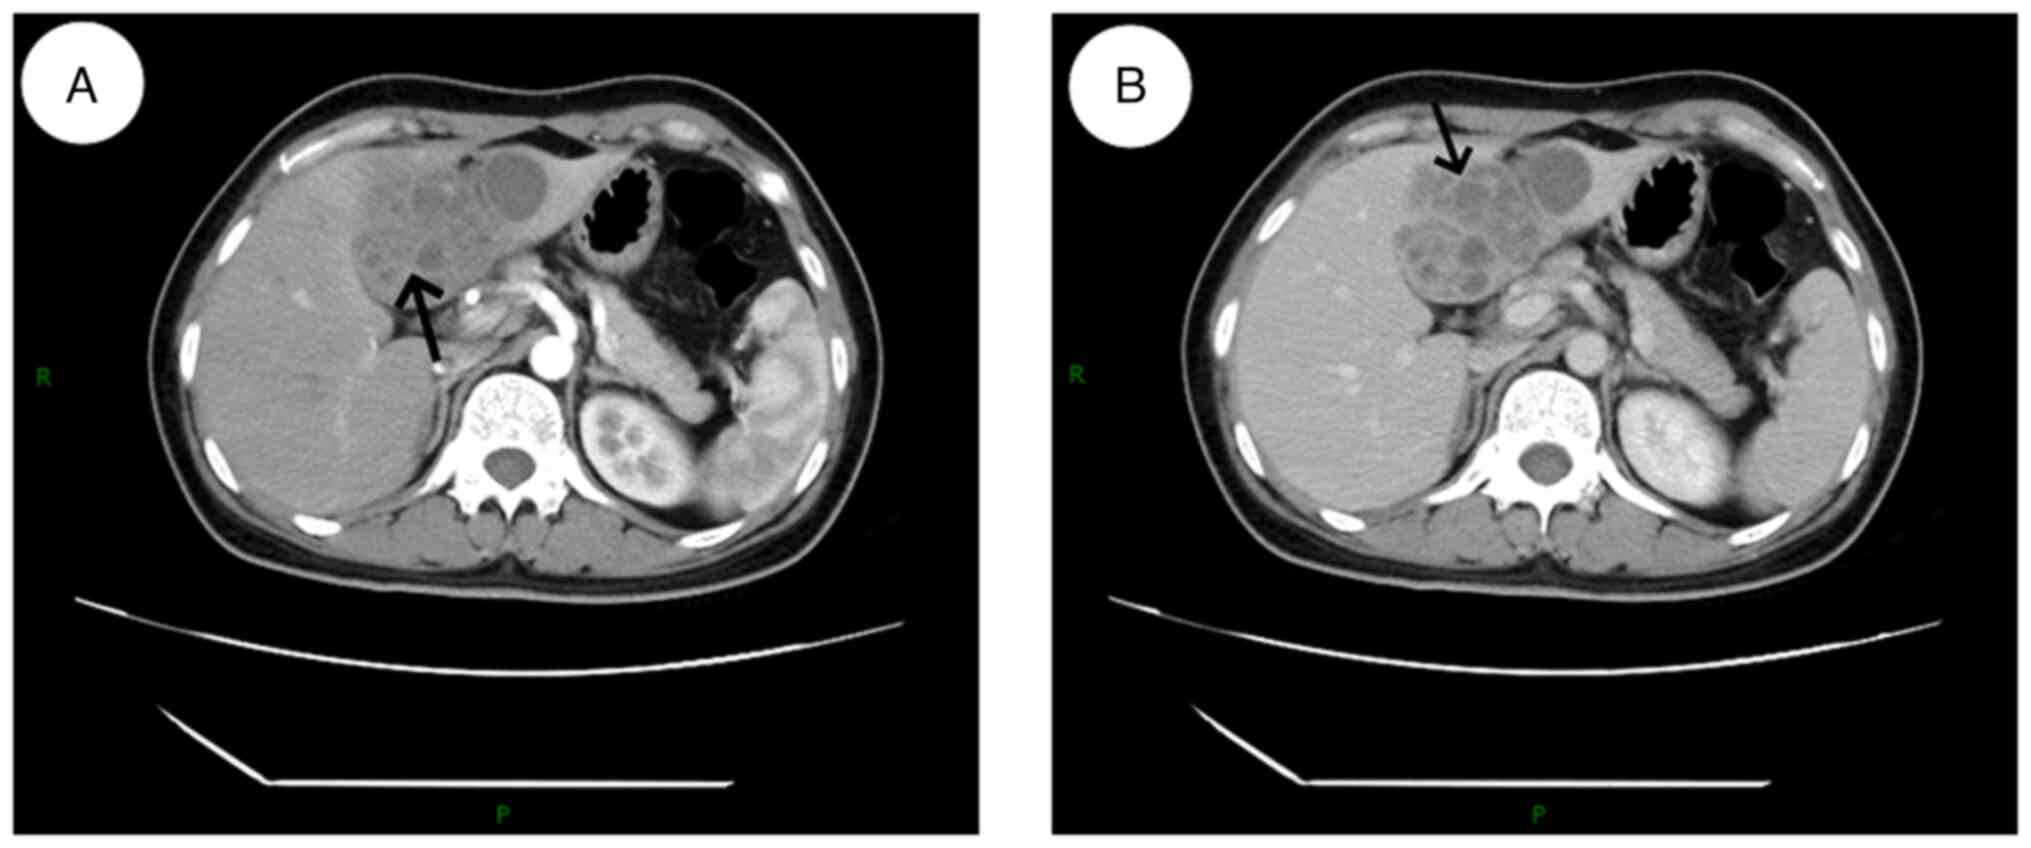

An upper abdominal computed tomography (CT) examination revealed multiple rounded, small flaky hypodense lesions in the left lobe of the liver, some of which were fused, with a larger cross-section of ~58x54 mm. Enhanced scanning with edge and segregation enhancement and marked inhomogeneous enhancement of the hepatic parenchyma in the arterial phase around the lesions were observed (Fig. 1). The diagnosis indicated a lesion in the left lobe of the liver, considered to be of an infectious origin. A liver abscess was highly likely, although a tumor could not be ruled out.

Figure 1

Preoperative abdominal CT examination results. (A) Contract-enhanced CT scan of the liver in the arterial phase after iohexol injection, showing enhancement at the edges and septation (arrow). (B) CT images in the venous phase showing multiple quasi-circular, small, patchy, low-density lesions (arrow). CT, computed tomography; P, CT section was started from the posterior side; R, CT section was started from the right side.

In previous years, with the progress of medical imaging technology, CT and MRI have been widely used in the diagnosis of parasitic infections of the liver and biliary tract. Due to the non-specific clinical symptoms of Clonorchis sinensis infection, solely relying on the clinical presentation for diagnosis is challenging, emphasizing the importance of characteristic radiological findings (14). MRI findings typical of Clonorchis sinensis infection include diffuse dilation of the intrahepatic peripheral bile ducts, with larger and extrahepatic bile ducts remaining undilated (14,15). In the present case, high signal was observed on T2WI, and diffuse mildly dilated terminal bile ducts were observed both in the center and periphery of the lesion. This characteristic is attributed to Clonorchis sinensis predominantly infesting the terminal bile ducts, causing obstructions in the smaller peripheral ducts (13). The most common finding on MRI of Clonorchis sinensis is a diffuse mild dilatation of the small intrahepatic bile ducts without dilatation of the extrahepatic bile ducts (15). The patient in the present report exhibited small patchy low-density lesions within the liver on the preoperative abdominal CT, with enhanced margins and septation upon contrast scanning. The hepatobiliary and pancreatic MRI findings included mixed long T1 and T2 signals, inconsistent signal intensities with indistinct borders, small patches of short T1 signals, low signal intensity on T1WI and high signal intensity on T2WI. The enhanced scans revealed a progressive, mild to moderate, uneven enhancement within the lesion area.